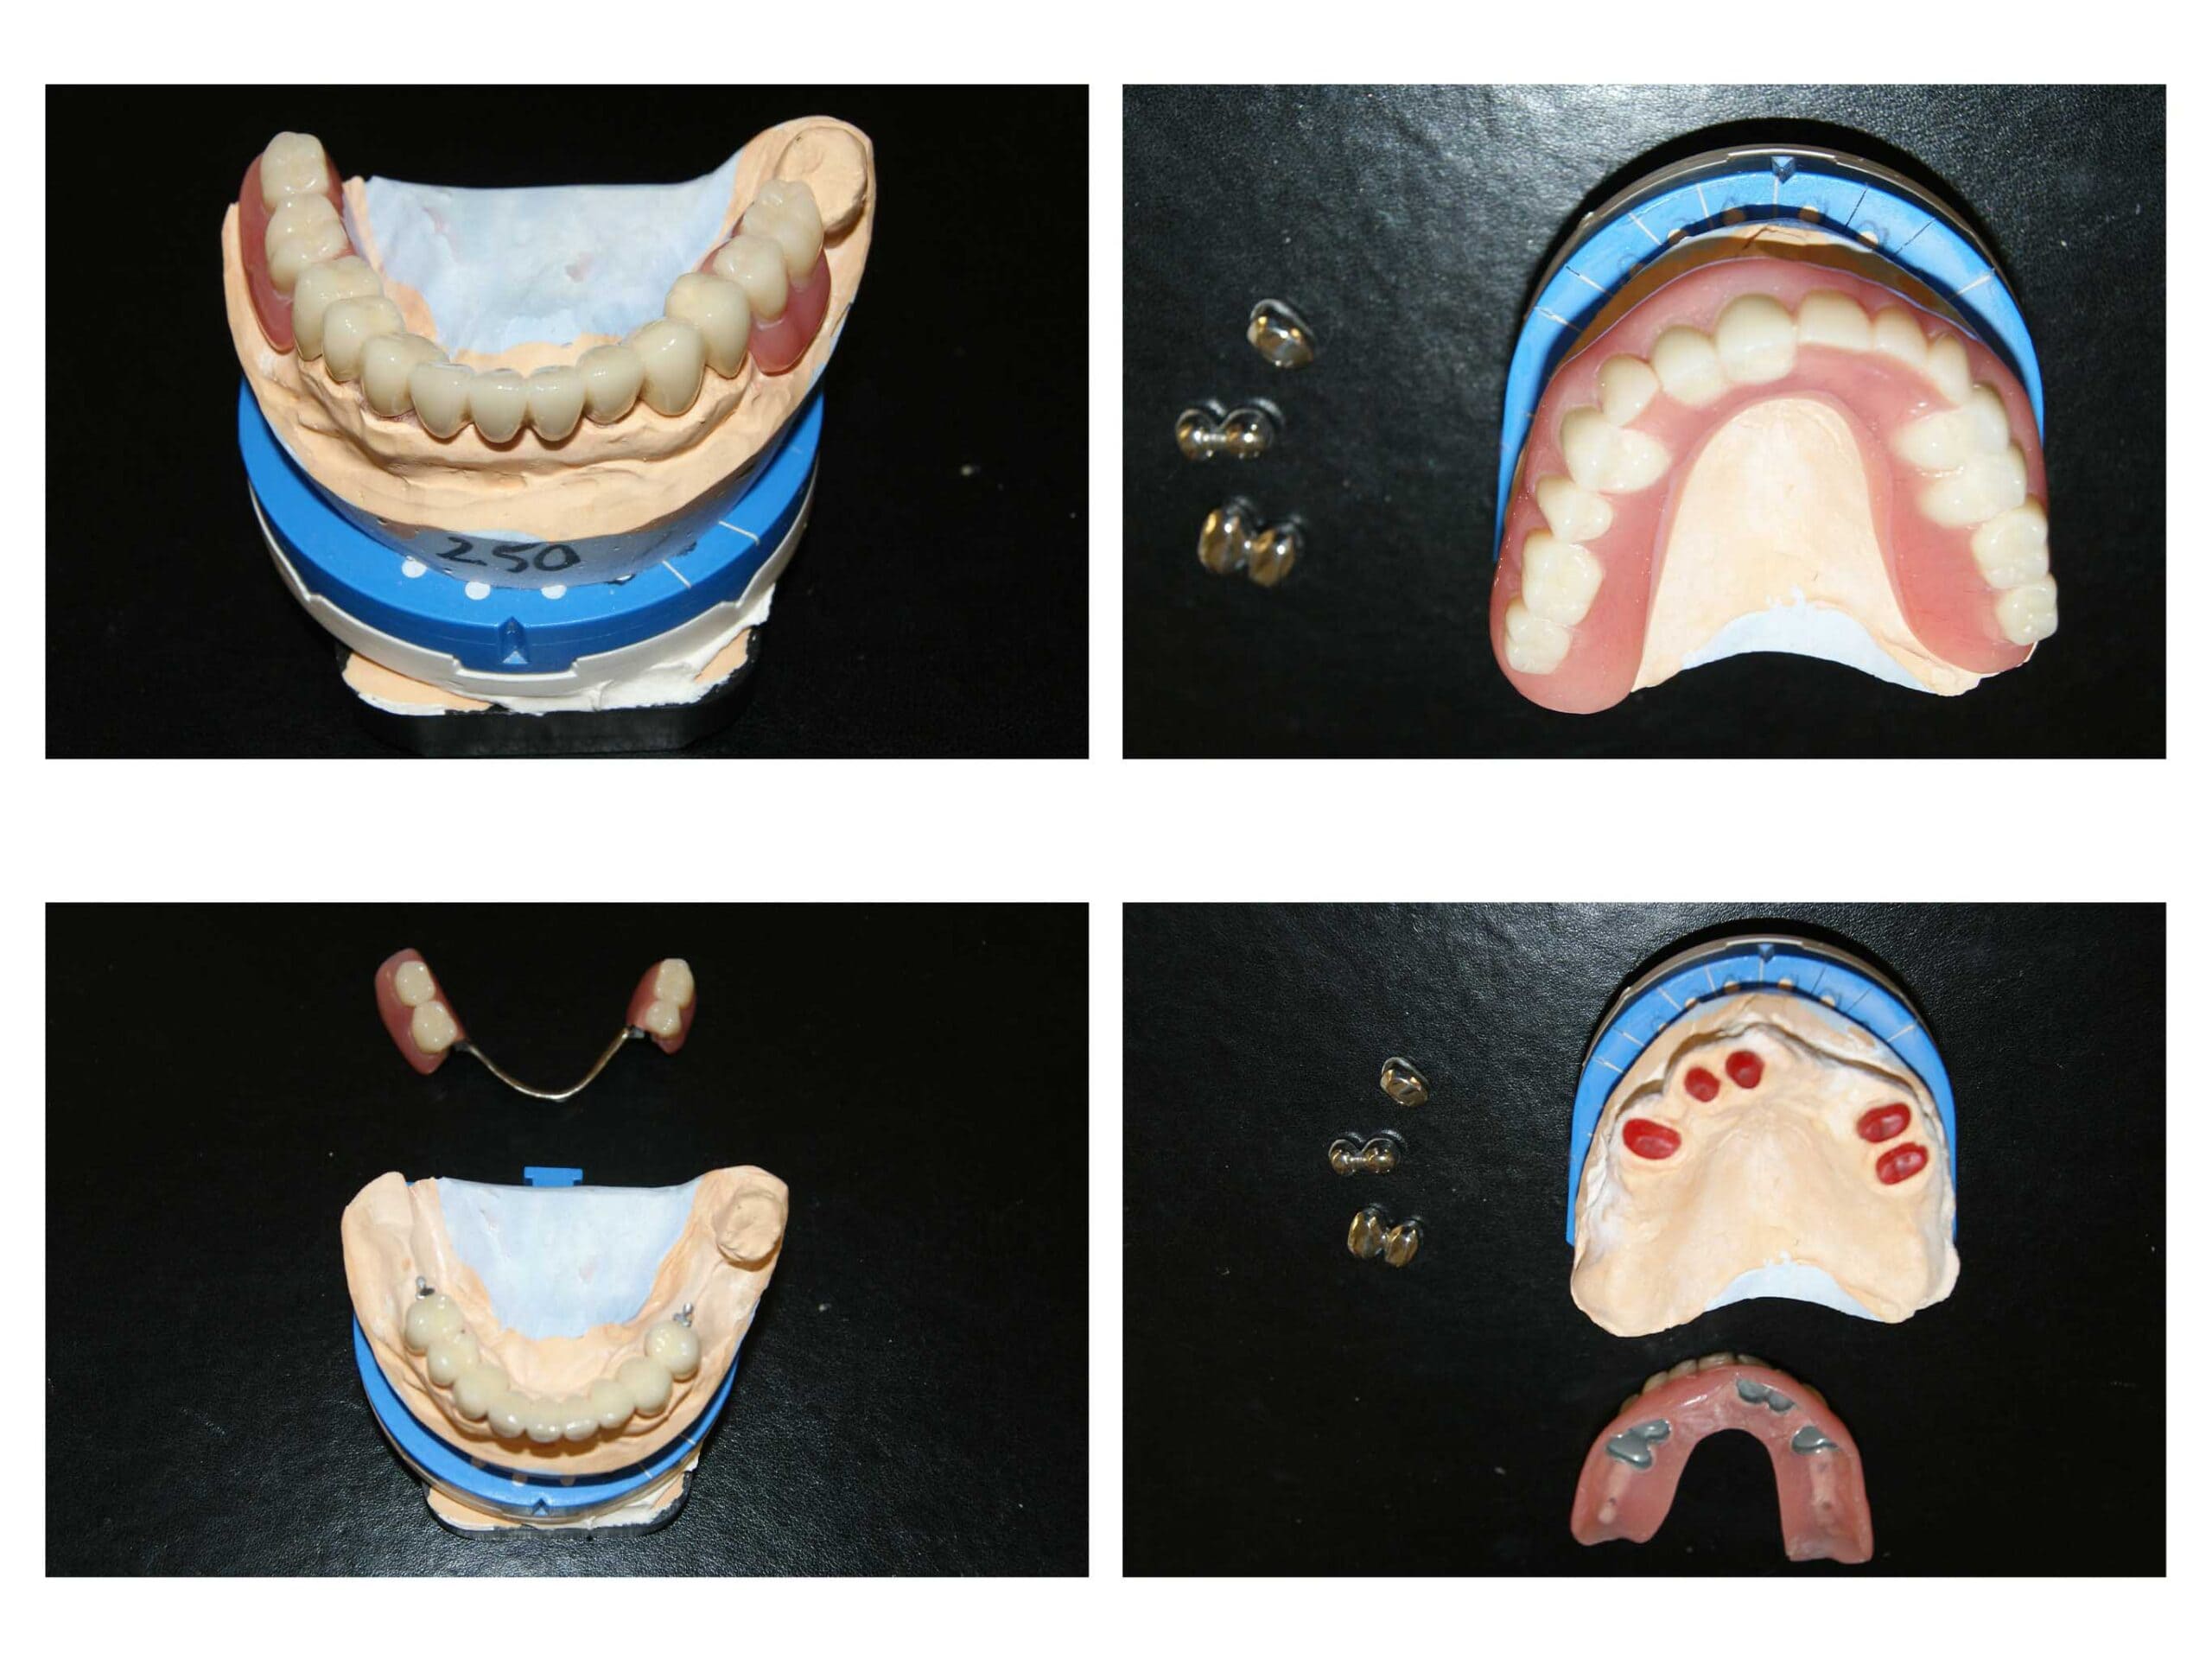

Reabilitare complexă și completă a dinților cu un accent grav de uzură, a dimensiunii verticale de ocluzie și a zâmbetului = restabilirea tuturor funcțiilor naturale

Tehnician – Happy 3Dent

Reabilitare orală complexă cu redimensionarea dinților cu grad accentuat de uzură. A fost necesară o soluție de provizorat de 6 luni de zile în care am verificat dacă pacientul se poate adapta cu înălțarea ocluzală propusă de noi. Am realizat tratamente de canal și reconstituiri atât pentru înălțarea dinților, cât și pentru tratarea proceselor infecțioase active. Rezultatele sunt remarcabile atât din punct de vedere funcțional cât și estetic